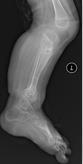

儿童陈旧性孟氏骨折

术前前臂侧位片